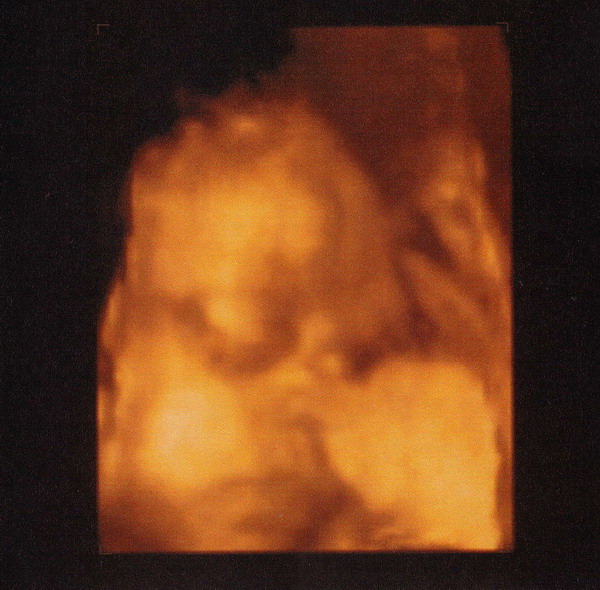

Timike jól van már 1200 gramm fölött van...íme egy profil...

Kép

most csak ennyire futotta...bocsánat ... :oops:

Tök jó ez a 4D UH kép Timikéről! :) Drukk, hogy rendeződjön a családi viszály!

hellóóó!!!üdvözlet Timikének, aki jól mutatta a pofiját a fotósnak! :)